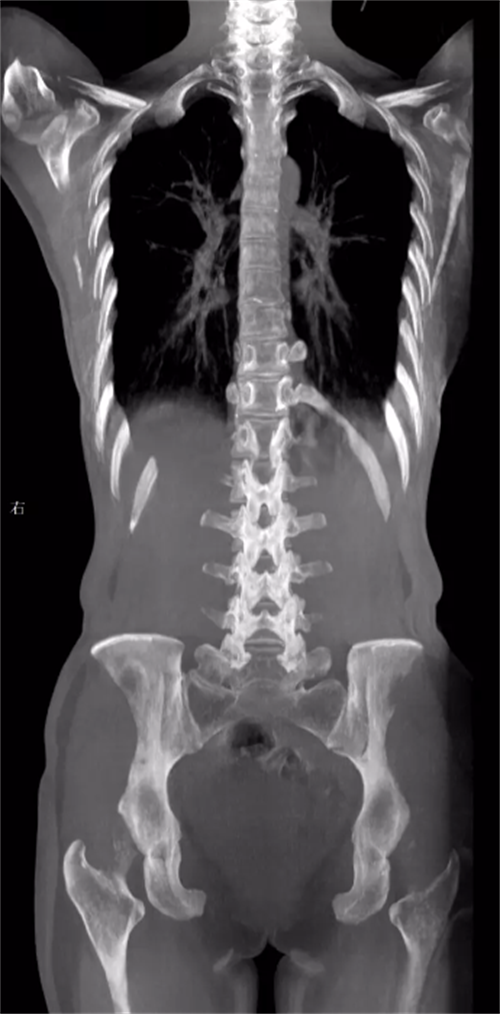

②三维化。三维是在动态的基础上实现的。那么为什么要将动态DR往三维化方向发展呢?原因就是目前常规动态DR在临床上有一定临床应用局限性。传统二维平片它极易受到投照角度以及摆位的影响导致漏诊和误诊,而三维检查能全面的呈现被检查部位在多个角度下的三维影像信息,能够提供精准且直观量化的测量数据辅助临床做出精准诊疗。(三维扫描重建图像)

在三维化研究的方向上,目前这几个厂家的技术算业界领先。首先就是安健科技国内首创的WR-3D,实现负重位下三维扫描与重建。WR-3D是通过CBCT原理来实现的,通过创新型的非等中心扫描实现业内最大FOV,解决业内其他厂家无法实现的一次扫描就可包含双侧髋关节、双下肢等的弊端。其次就是法国EOS,当然它实现三维扫描的原理与安健大不相同,它是通过两组垂直放置的探测器自上而下扫描,获得正侧位的影像,在通过正侧位影像来做模板匹配,拟合出三维影像。最后就是涛影,它的原理类似于G型臂,通过双平面系统扫描,将双平面影像导入骨与关节三维分析工作站,获得三维图像。不过值得一提的是,这三个厂家目前只有安健科技的WR-3D是真三维扫描。(左边图像为安健科技WR-3D,右边图像为法国EOS)

总的来说三维摄影不仅具备动态DR的全部功能,且较动态DR的二维扫描,三维摄影能够提供更加优质的临床图像以及精准的骨关节参数信息,同时可以补位CT和MRI,实现CT和MRI无法满足的负重位下三维扫描与重建,同时相较于CT,且三维DR还具有比CT剂量更低的优势。